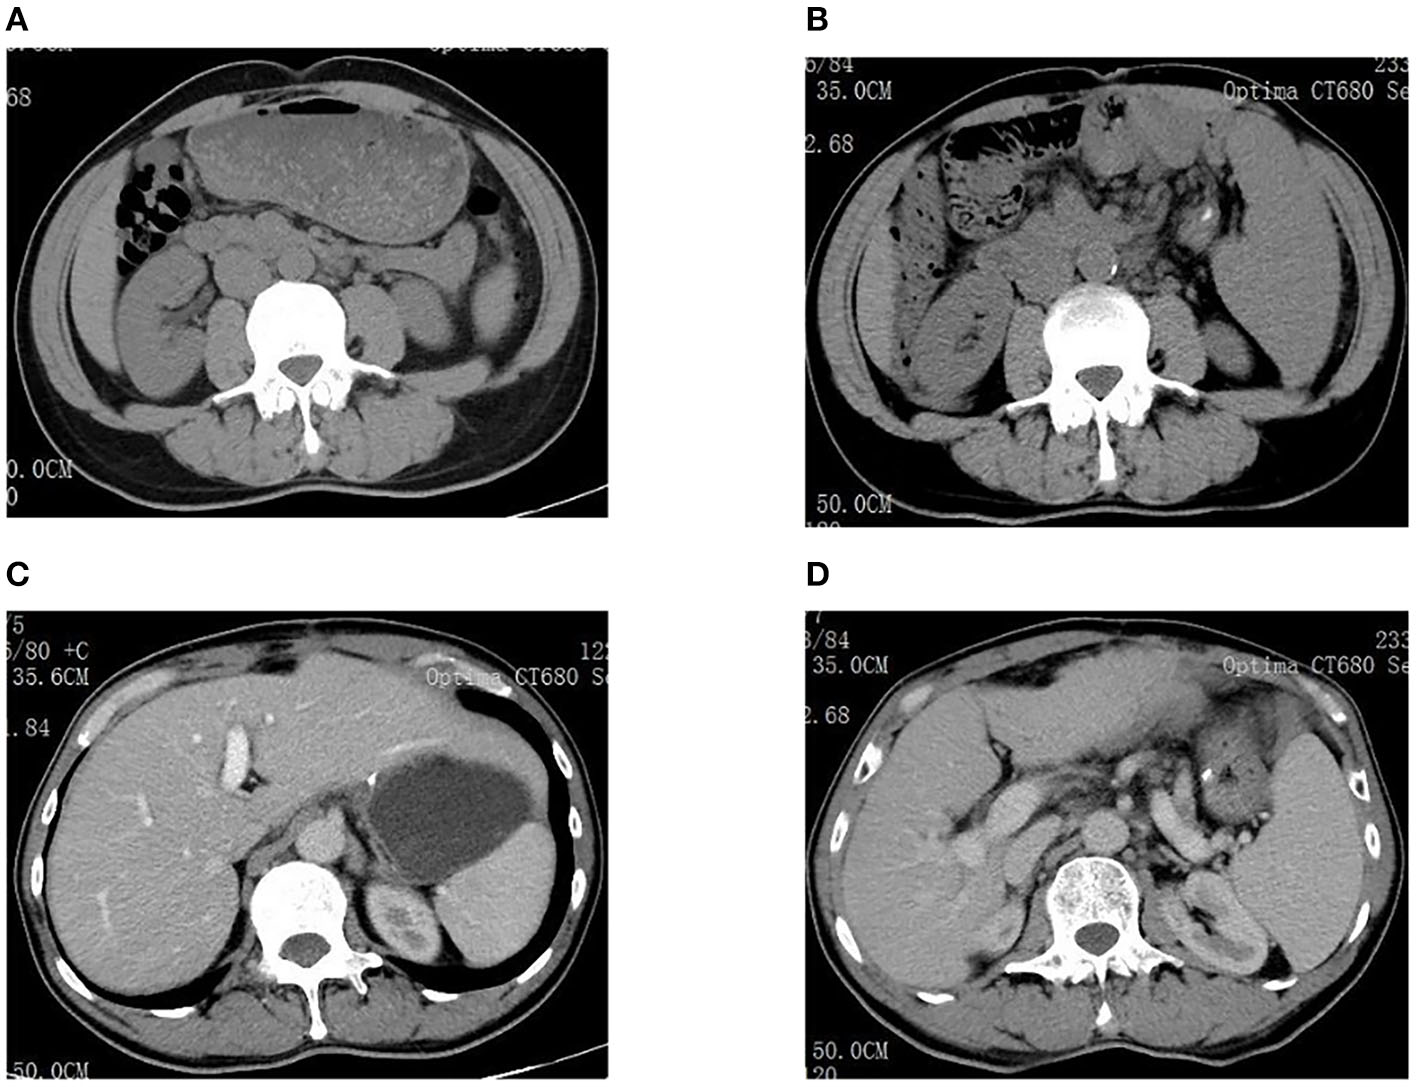

Examinations of the patient conducted over the past 5 years have revealed significant changes when compared to the full-abdomen routine scan performed before the surgery in 2018 and post-surgery in 2022 (Figure 2). Notably, the portal vein has markedly widened, and the spleen has enlarged substantially. A gastroscopy conducted before the surgery in 2018 indicated the absence of significant esophageal and gastric varices. However, subsequent annual routine examinations from 2019 to 2023 have shown a progressive worsening of esophageal and gastric varices (Figure 3). The patient initiated carvedilol (6.25 mg peros quaque die) therapy in 2020, but the disease continued to advance. Platelet count, which began to decline after chemotherapy, has not yet returned to normal levels (Figure 4). A PubMed literature search unveiled numerous documented cases of INCPH induced by oxaliplatin.

Figure 2. (A) Spleen size was normal before surgery in 2018. (B) The spleen was significantly enlarged in 2022. (C) Liver size was normal before surgery in 2018. (D) The portal vein dilated significantly in 2022.